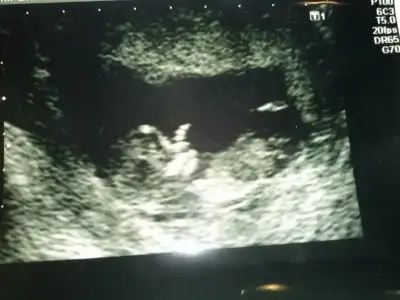

• CAM01705[1].webp

CAM01705[1].webp

11,3 KB · Görüntüleme: 91